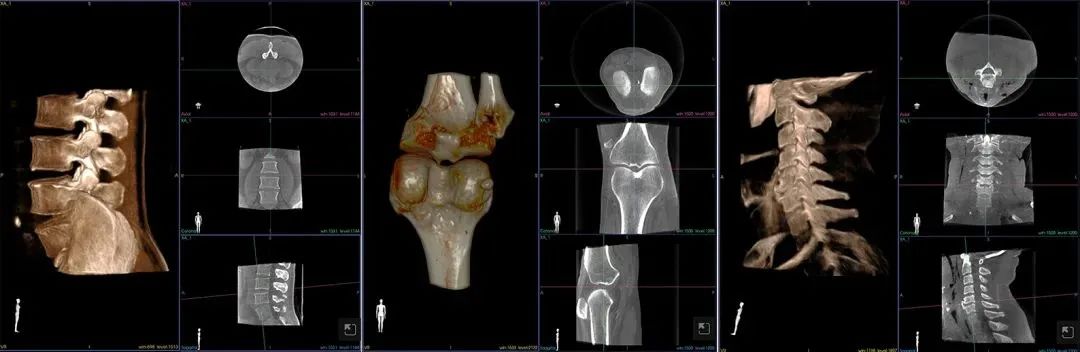

另外,刘新宇教授对歌锐术中CBCT也给予了高度评价。他表示,歌锐CBCT仅用12s~14s即可完成影像扫描及三维重建,节省了时间,图像精度达0.16mm,满足了外科精准手术的需求,此外,偏心投照的设计十分人性化,为通道穿刺等临床工作提供了便利。

此外,歌锐高级临床专家Raymond团队也尝试和模拟了全流程微创手术机器人辅助下针对颈椎、胸椎等多个部位的多种入路和术式,均顺利完成并取得了成功。